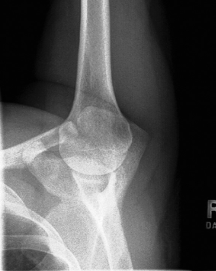

is this a normal or dislocated shoulder? how do you know?

normal, head of humerus superimposed over base of Y